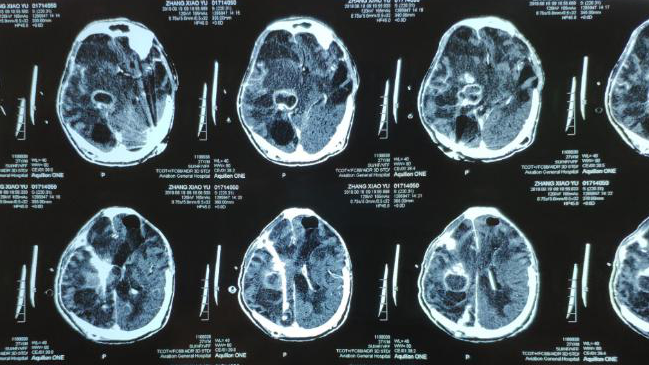

近日,傅继弟教授颅内感染团队(以下称该团队),接诊了一名外省转来的危重颅内感染患者。6个脓肿如何处理?由于运用显微手术技术,术中完整剥离了脓肿壁,最大限度保护脑组织,大大减少病变周围脑组织损伤,患者在术后3天便恢复了意识!